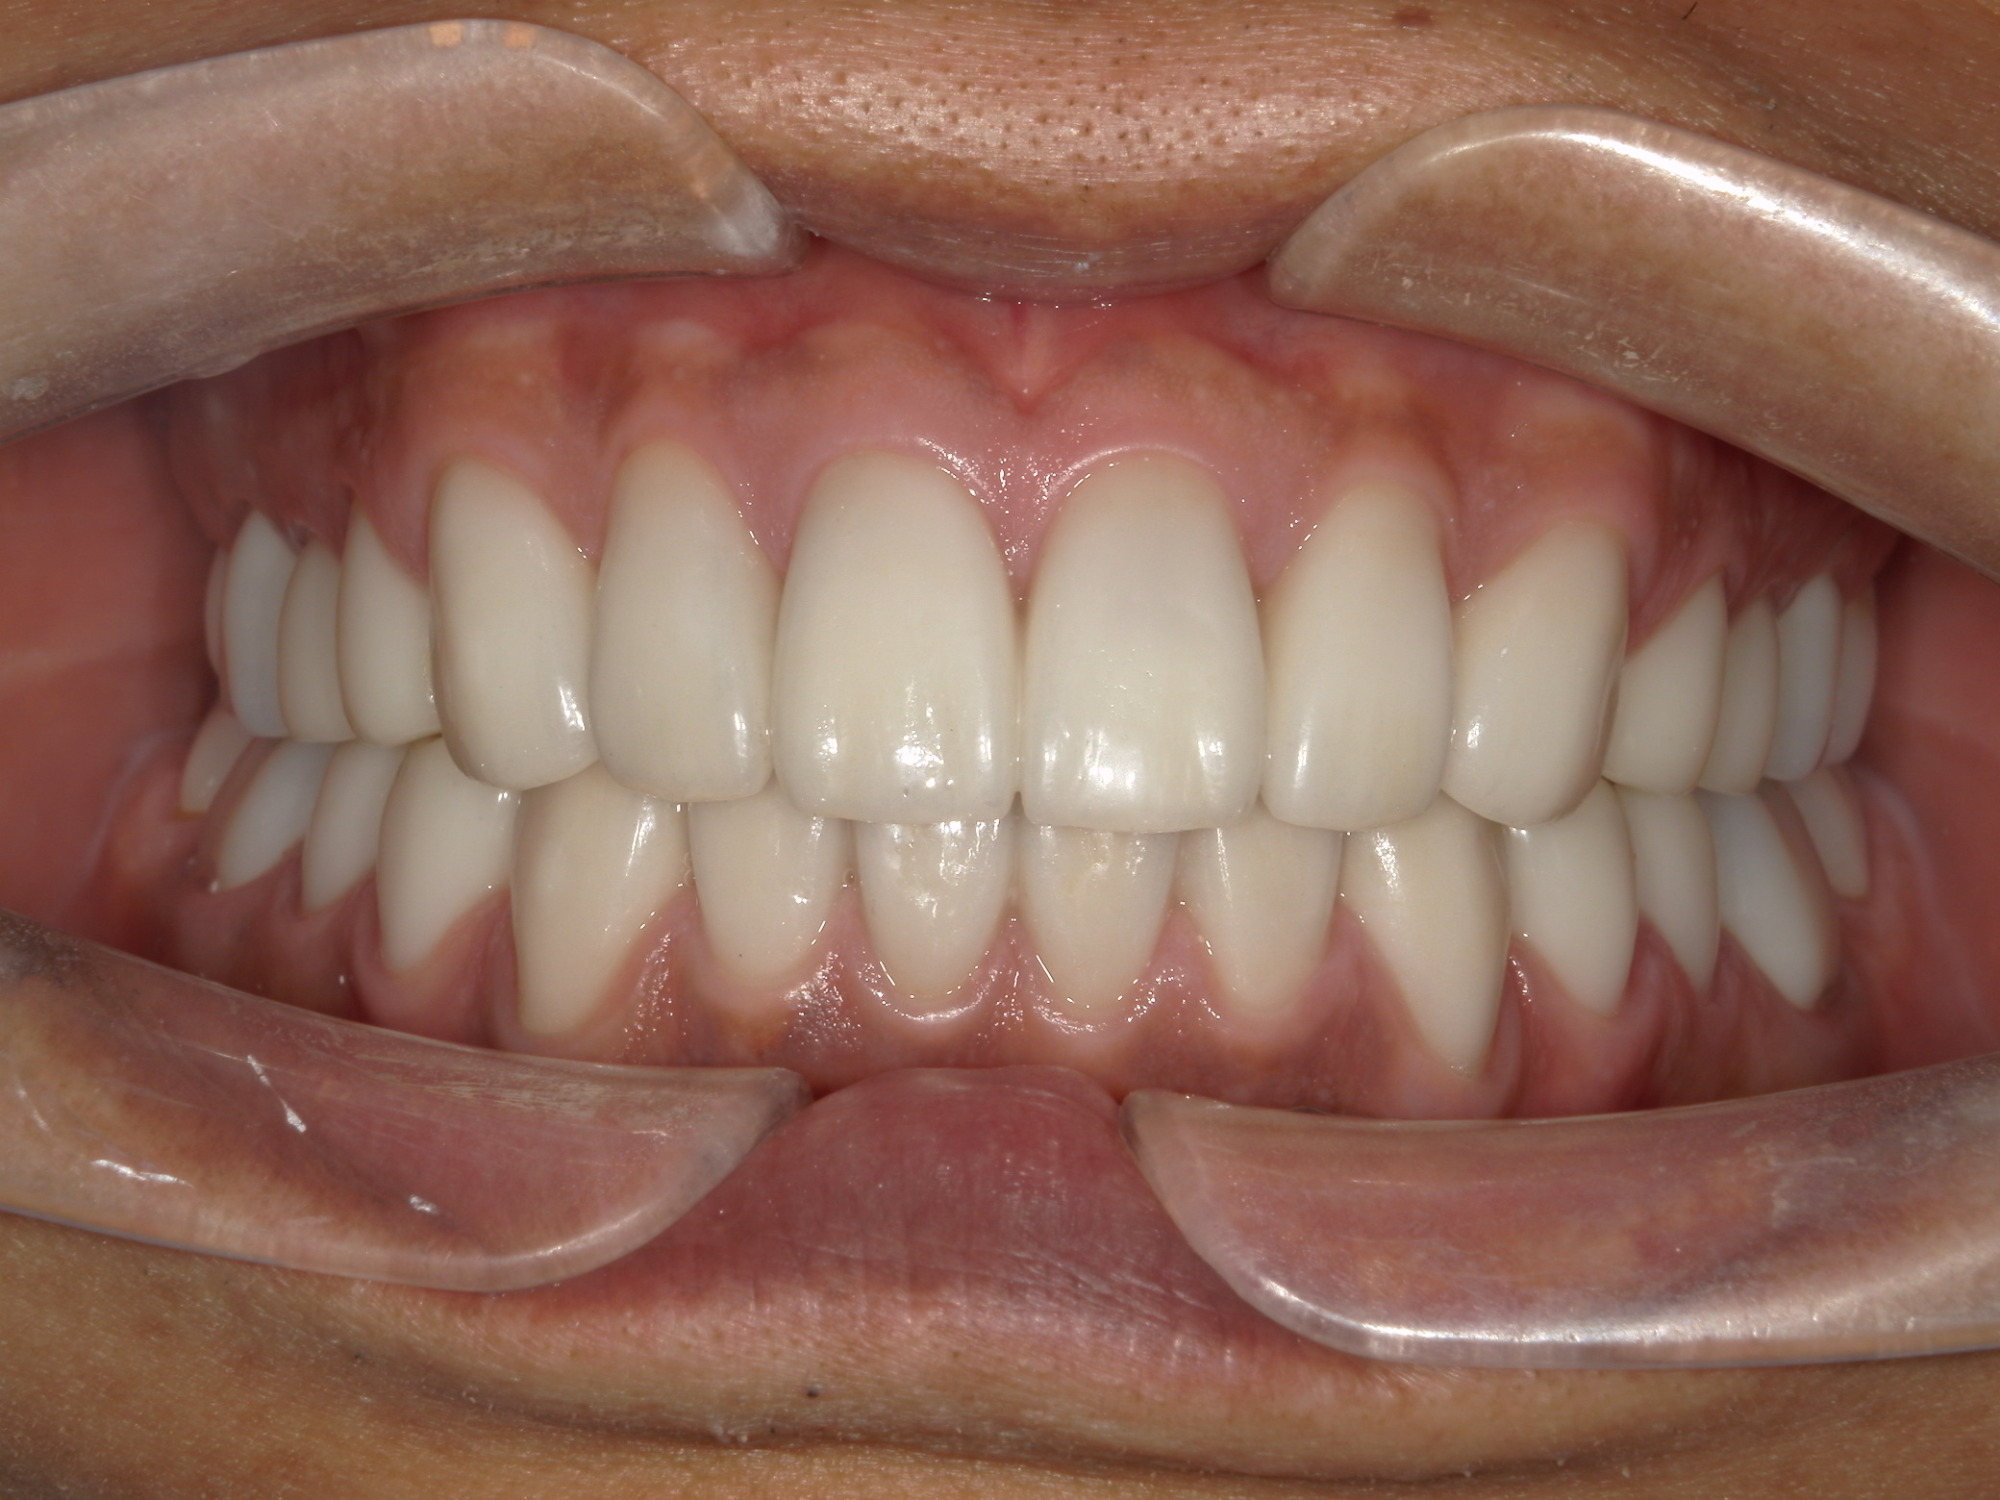

全顎的なセラミック治療によって、審美及び機能咬合回復を行った症例

患者様情報 40代男性 患者様のお悩み 見栄えが気になる、噛み合わせが気になる 治療概要 詰め物・被せ物 提案内容 全顎的に歯が噛耗しており審美的にも、機能的にも改善が必要な状態であった為、全顎的な補綴治療を提案させてい […]